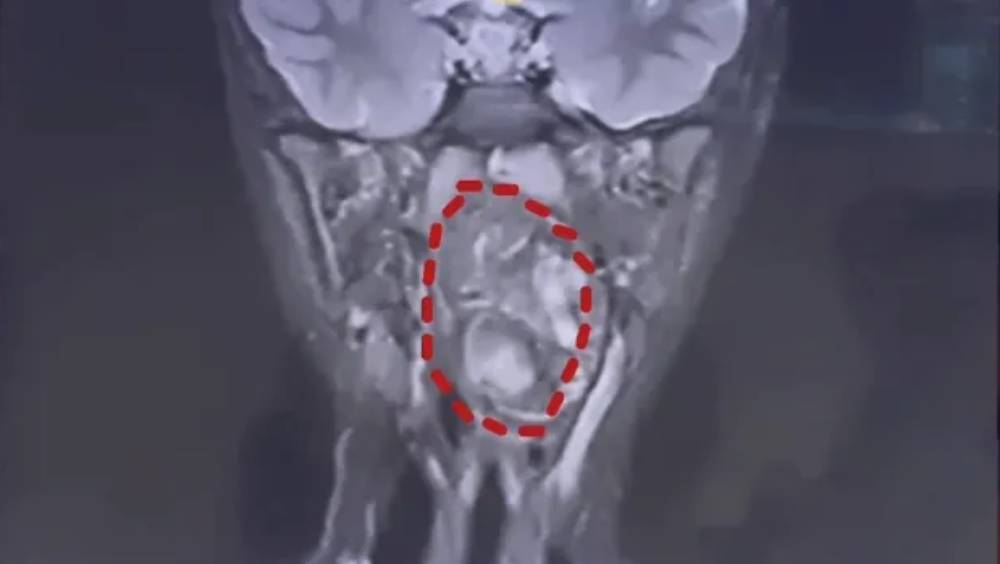

- 腫瘤大小達6.6厘米,幾乎完全堵塞了僅約8厘米的口咽腔,有窒息風險。

負責診治的耳鼻咽喉頭頸外科副主任陳超醫生解釋,該腫瘤是由生殖細胞演變而成的畸胎瘤。醫生指出,從中可以看到脂肪和軟骨組織,這本應是一對雙胞胎,一個正常發育,另一個則可能殘留在喉嚨處,發育成了畸胎瘤。此類腫瘤多為良性,但生長在兒童咽喉部且體積如此巨大則極為罕見。